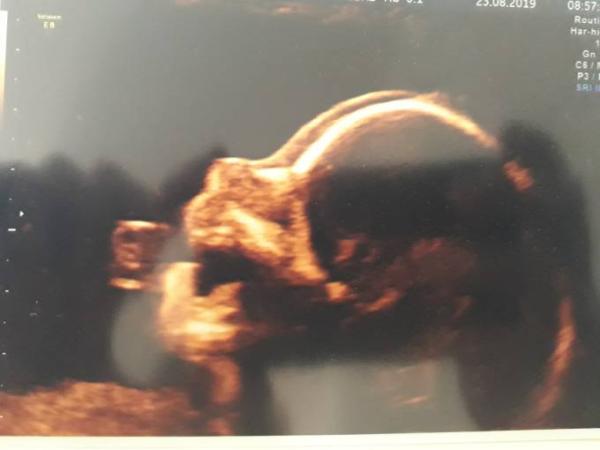

Hey, bei uns war heute auch der Termin zur Feindiagnostik wegen den Plexuszysten. Es ist alles gut eine Zyste ist sogar schon verschwunden. Und alles andere ist ganz normal, keine Hinweise für irgendeine Behinderung Und es gab ein Outing: wir bekommen ein Mädchen

Bild zu FD und Outing :-) - Forum für Januar - Mamis